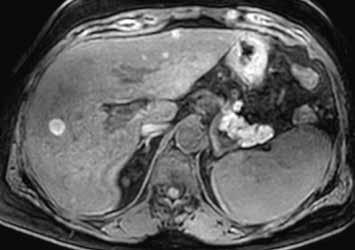

Nativně je v játrech ložisko, které je na CT hypodenzní (4), na MR izointenzní (5).

Na CEUS je v arteriální fázi patrný v levé polovině obrázku typický centrifugální charakter sycení ložiska, které je vidět v pravé polovině obrázku v B -módu (jako hypoechogenní) (6–8). Na CT (9) i MR (10) se ložisko (z obr. 4, 5) sytí homogenně, vyjma centrální vazivové jizvy, která zůstává hypodenzní.

V portovenózní fázi je ložisko izodenzní na CT (11), respektive izointenzní na MR (12).